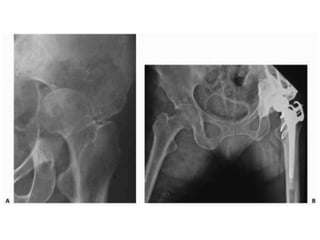

Lobulated partially ill-defined lytic lesion of the proximal Humerus

• Peritrochantric femuris the most likely to cause serious morbidity and therefore threshold for prophylactic intervention is low • Femur account for 65% of pathologic fracture • Humerus and vertebra also require special attention • Mirels scoring system is used to predict the pathological fracture risk. • Clinical prediction of survival is also important which depends on: • Primary site • Number of bone mets. • Involvement of viscera • Haemoglobin level

• Upper Extremity •Scapula, clavicle – non operative • Proximal humerus – prosthesis (long stem), intramedullary nail with multiple screws • Humerus Diaphysis – locked IM nail > plating • Distal humerus – prosthesis, retrograde flexible IM nails > bicondylar plating • Forearm – Rare. IM nails or plating

• Lower Extremity •Acetabular – reconstruction with appropriate prosthesis • Femoral neck – hemi- or THR. Cemented. Long stem • Intertrochanteric – recon nail or prosthesis > DHS • Sub trochanteric – locked IM nail • Femur shaft – locked IM nail preferably cephalo- medullary • Around the knee – locked plating > retrograde nailing